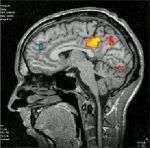

Чрез функционално магнитно-резонансно изследване лекари от University of California установили, че педиратичните пациенти с биполярно разстройство имат активация на лимбичния регион, а тези с хиперактивност на фронто-субкортикалната мрежа при извършването на паметови задачи.